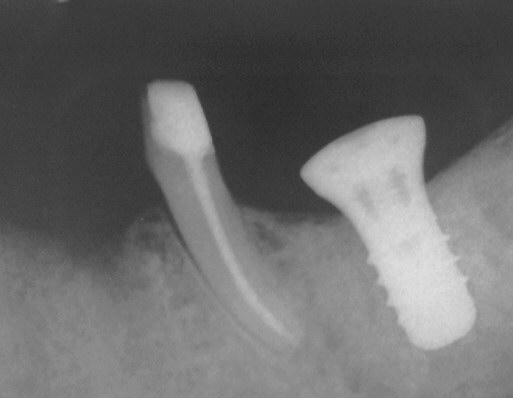

Bei Bruxern ist auffällig, dass im Oberkiefer sehr häufig die palatinale(n) Wurzel(n) so stark geschädigt wird/werden, dass sie nicht erhalten werden kann/können. In diesem Fall wies der Zahn 17 einen Lockerungsgrad von L=II auf. Bei subtiler klinischer Untersuchung zeigte sich, dass der Zahn in diesen Fällen bei Belastung deutlich nach palatinal, kaum jedoch nach bukal kippte (bukkale Knochenwand vollständig erhalten, palatinale Wurzel nur noch im Bindegewebe). Nach Hemisektion und Wurzelfüllung unter sorgfältiger Desinfektion mit daraus resultierender Beseitigung  der Trifurkation, erreichte der Zahn wieder L=0. Weil es sich nichtsdestotrotz um einen schwachen Pfeiler handelte, haben wir ihm zur statischen Unterstützung nach internem Sinuslift  ein Implantat (ITI 10mm lang, Durchmesser 4.3mm) an die Seite gestellt.

Kontrollaufnahme ca. 3 Jahre nach Eingliederung der Brücke 13-15-16,17 und 4.5 Jahre nach internem Sinuslift mit Cerasorb (Klick!).